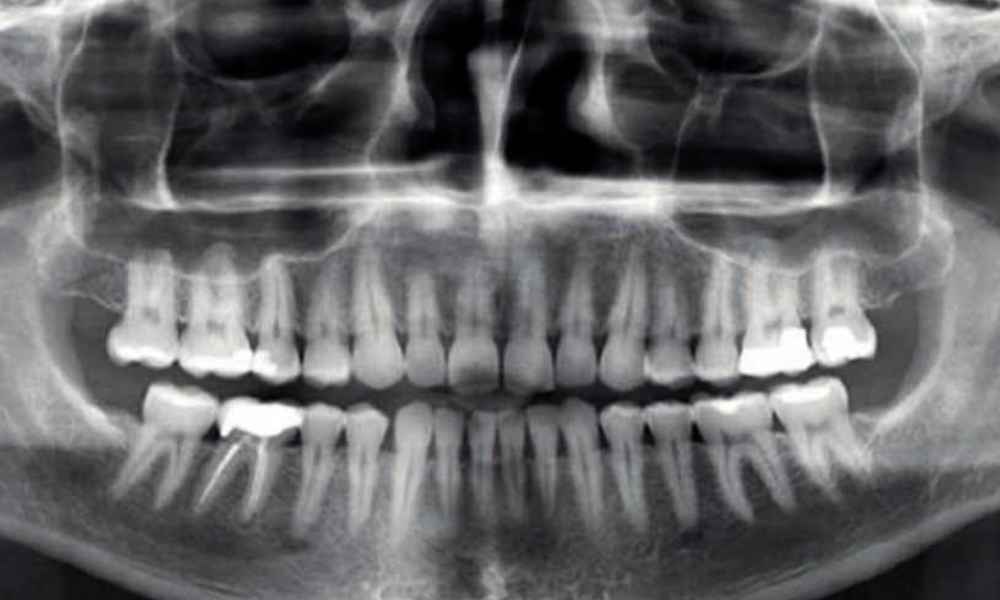

DIAGNÓSTICO 2D

La ortodoncia, históricamente ha usado las radiografías tradicionales como examen complementario de los pacientes. Este método se sigue usando, principalmente en los niños, aportando mucha información relevante.